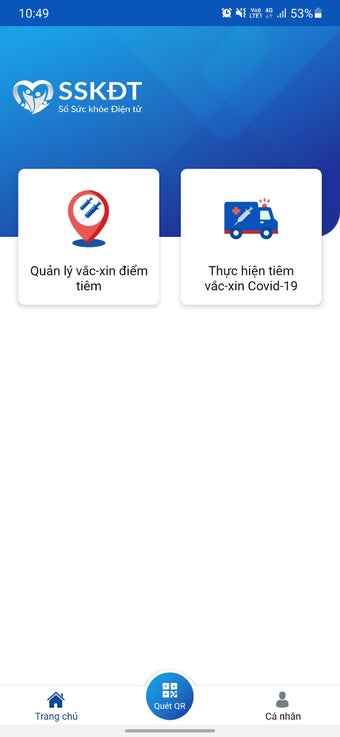

บันทึกข้อมูลสุขภาพอิเล็กทรอนิกส์สำหรับแพทย์เป็นแอปพลิเคชันแอนดรอยด์ที่พัฒนาโดย Văn phòng Bộ Y tế Việt Nam แอปพลิเคชันฟรีนี้ออกแบบมาเพื่อบุคลากรทางการแพทย์และแพทย์เพื่อเก็บข้อมูลผู้ป่วย ทำการฉีดวัคซีน เพื่อลดความแออัดที่จุดฉีดวัคซีน และลดความเสี่ยงในการติดเชื้อ COVID-19 นอกจากนี้ยังช่วยในการแก้ไขปัญหาสุขภาพของประชาชนอย่างรวดเร็ว

ด้วยบันทึกข้อมูลสุขภาพอิเล็กทรอนิกส์สำหรับแพทย์ บุคลากรทางการแพทย์สามารถวินิจฉัยและรักษาผู้ป่วยได้อย่างง่ายดาย โดยให้การดูแลสุขภาพอย่างครบถ้วนและต่อเนื่อง ตรวจจับโรคในระยะเริ่มต้น และให้การรักษาทันเวลา ซึ่งเป็นปัจจัยที่สำคัญในการเพิ่มประสิทธิภาพในการรักษาและลดค่าใช้จ่ายด้านสุขภาพสำหรับประชาชน